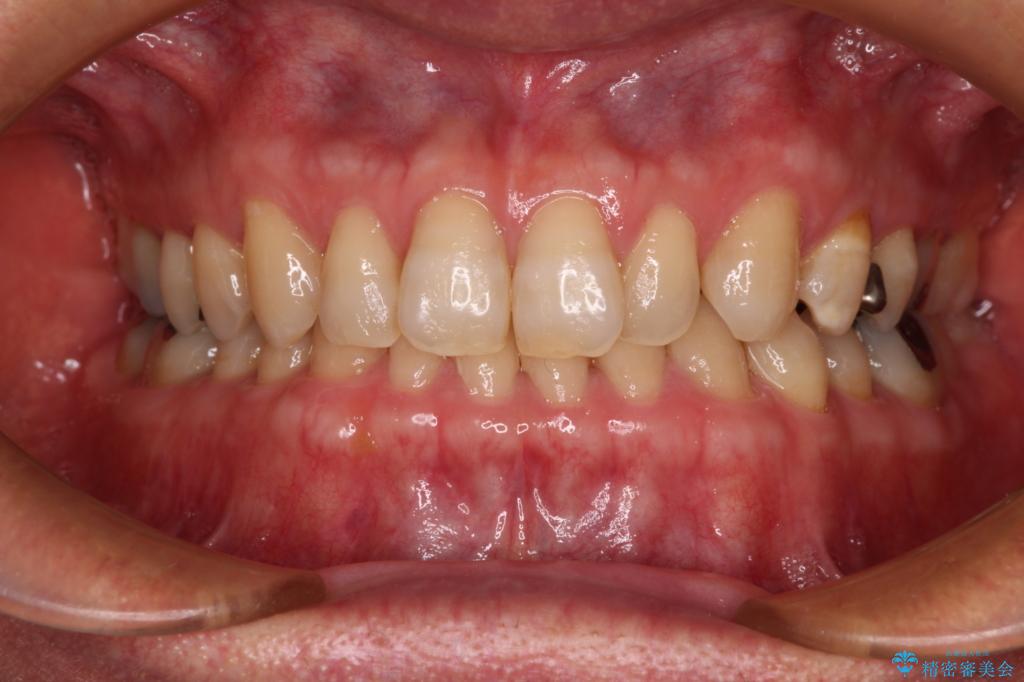

手前に傾斜している奥歯をワイヤー装置で立ち上がらせ、咬み合わせの高さを挙上することで突き上げを解消し、空隙歯列を改善していくこととしました。

ディープバイトが改善され、睡眠時の食いしばりも緩和され、顎への負担が軽減されました。